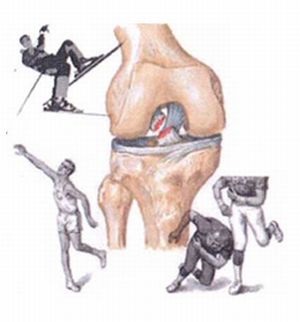

Picioarele sunt adesea răniți în sportivi implicați în stare de funcționare, fotbal, hochei, schi.

Adesea, instabilitatea manifestată după accidente rutiere.

Acesta nu este doar sportivii, dar, de asemenea, despre oameni obișnuiți care, în instabilitatea genunchiului trebuie să protejeze în mod constant la nivelul membrelor de stres ridicat chiar și la mersul normal.

De multe ori, bolnavii sunt picioare slabe după alpinism pașii și schimbarea bruscă ședinței postură într-o poziție în picioare.

Imaginea vieții pacientului este fundamentală pentru a clarifica cauzele bolii și alegerea direcția corectă de tratament. Sportivii se antreneze din greu timp de mai mulți ani, este dificil să accepte faptul că sportul a fost în trecut. Dar, din păcate, realitatea este diferită.